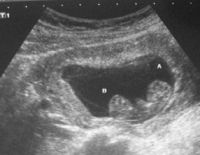

Đo độ mờ da gáy là gì và ý nghĩa khi thực hiện trong thai kỳ

Một trong những kiểm tra cần thiết trong thai kỳ mẹ cần thực hiện là đo độ mờ da gáy. Việc đánh giá thai nhi có nguy cơ bị bệnh Down hay không chính là nhờ vào phương pháp này. Tuy nhiên, tính chính xác...